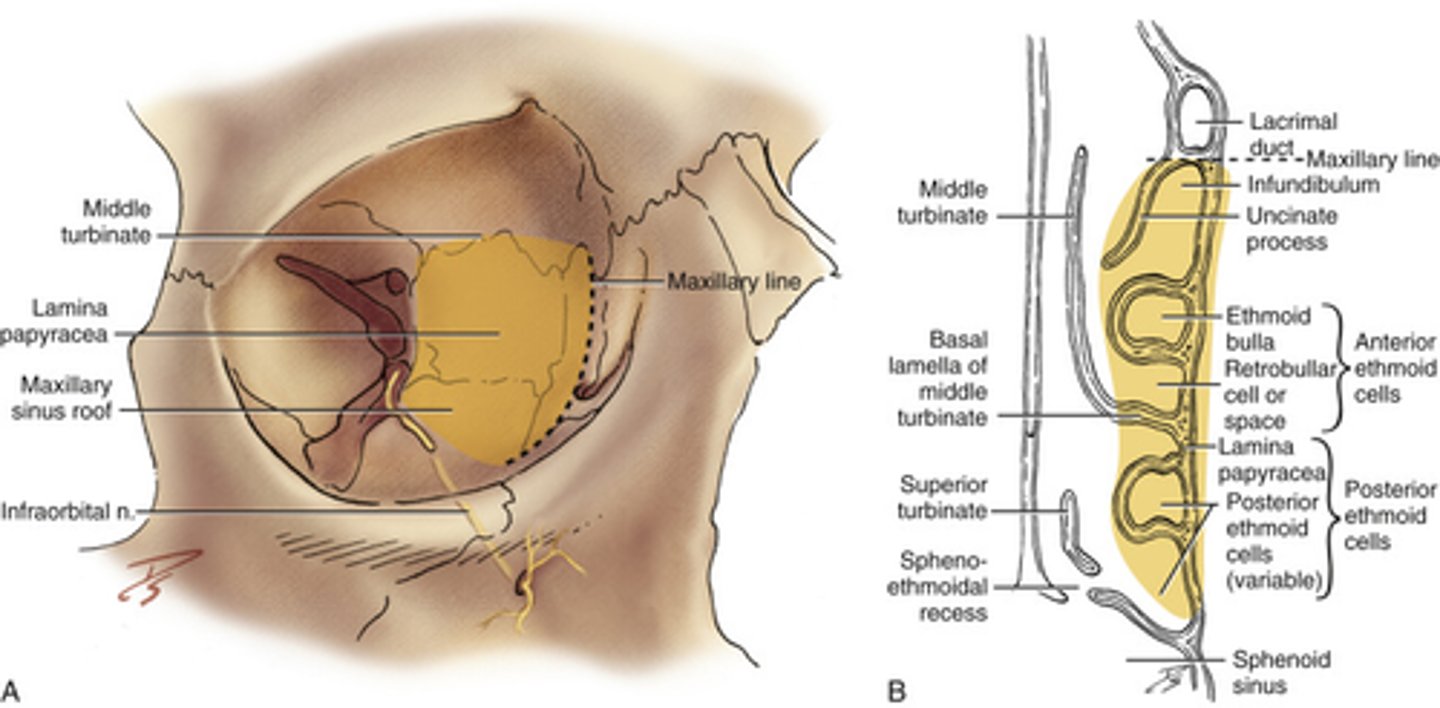

Orbital plate

Lateral surface forming part of the orbit.

Lacrimal papyracea

Thin plate of bone in the eye socket.

Ethmoid air cells

Air-filled spaces within the ethmoid bone.